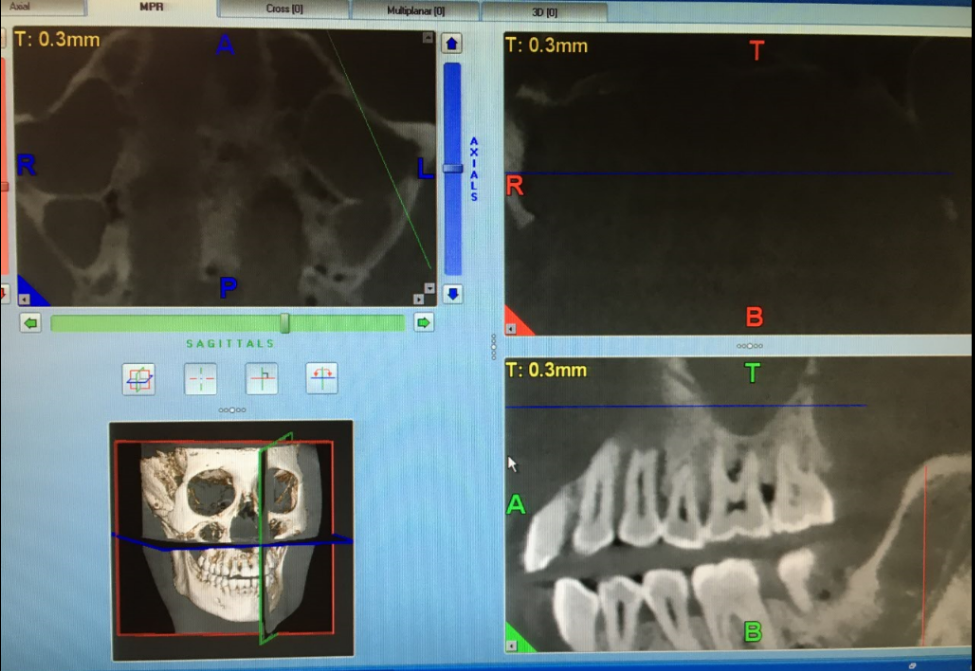

牙科細節(jié)頭部模型專用于牙科X線設備而設計,如:全景牙科,頭頜面攝影,牙科錐束CT,或一般三維成像應用

對于牙科X光檢查中的偽影評估,包括牙齒修復或嵌體??梢愿鶕?jù)客戶要求添加特定的牙齒修復,材料填充或牙冠。

適用于全景牙科,頭頜面攝影,牙科錐束CT,三維成像應用模型

4. 模式可顯示完整的頭部骨骼解剖結構,但是沒有軟組織或軟骨解剖,沒有氣管